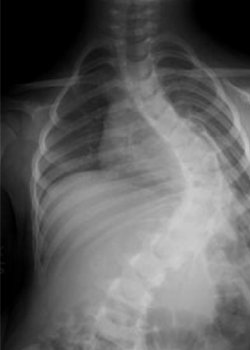

Children who develop scoliosis early in life are still growing. Most surgery to correct scoliosis involves fusion of the spine, therefore stopping its growth, so this cannot be done on young children as their spines are still developing.

If the spine is fused and the child is still growing, the ‘crank-shaft phenomenon’ could occur. This is when the front of the spine continues to grow, resulting in further rotation and curvature of the spine.